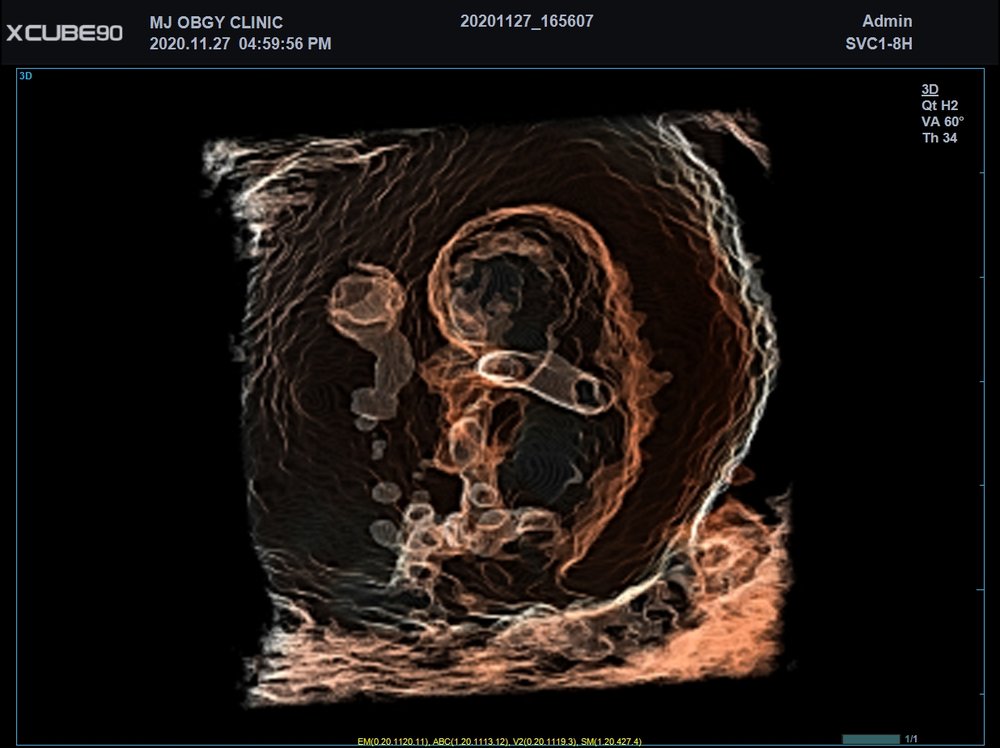

Volumen Konvex-Sonden

• SVC1-8H (1-8 MHz) für Ultraschalluntersuchungen in Bereichen Abdomen, Geburtshilfe, Gynäkologie, Urologie, Pädiatrie, EM